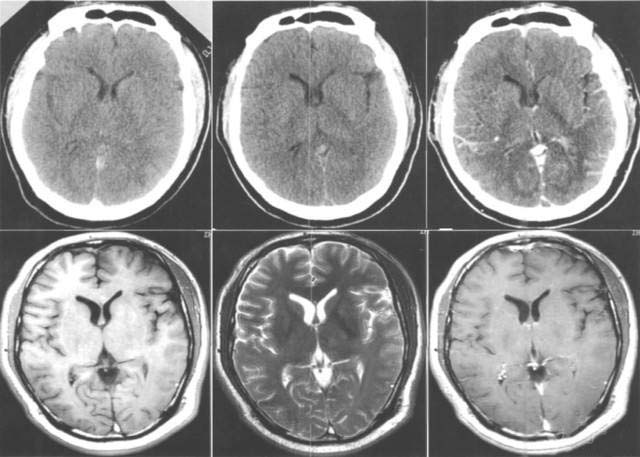

康復(fù)案例

病例一

患者徐某某 ,女,55歲,家住濰坊市經(jīng)濟開發(fā)區(qū)馬家埠村。患者被家屬發(fā)現(xiàn)突然意識不清,呼之不應(yīng),惡心、嘔吐,右側(cè)肢體癱瘓。

家屬撥打120求救電話之后,由120救護車將患者接到市立醫(yī)院急診科。經(jīng)顱腦CT檢查后診斷為“腦出血”,主管醫(yī)師迅速對該患者進行了腦出血微創(chuàng)手術(shù),病情及時得以控制,病人轉(zhuǎn)危為安。手術(shù)12天后,病人能夠自行進食,獨立完成更衣、穿鞋等動作,自行走出病房并順利出院。事后,患者家屬送來錦旗表示感謝。

病例二

患者玄某某,女,90歲,濰坊市經(jīng)濟開發(fā)區(qū)邢石村人。2014年3月13日,患者突感眩暈,后重重摔倒在地,出現(xiàn)昏迷。家屬發(fā)現(xiàn)后立即撥打120求救,我院迅速派出救護車前往救治。

患者被接到醫(yī)院后,觀察出現(xiàn)呼吸不律且有呼吸短暫停止的跡象,瞳孔大小不等,情況十分危急。經(jīng)顱腦CT后診斷為“腦出血”。主管醫(yī)師當(dāng)即決定,為患者馬上進行腦出血微創(chuàng)手術(shù)。術(shù)后10天,患者意識清醒,身體指征正常,短暫休養(yǎng)后得以恢復(fù)出院。